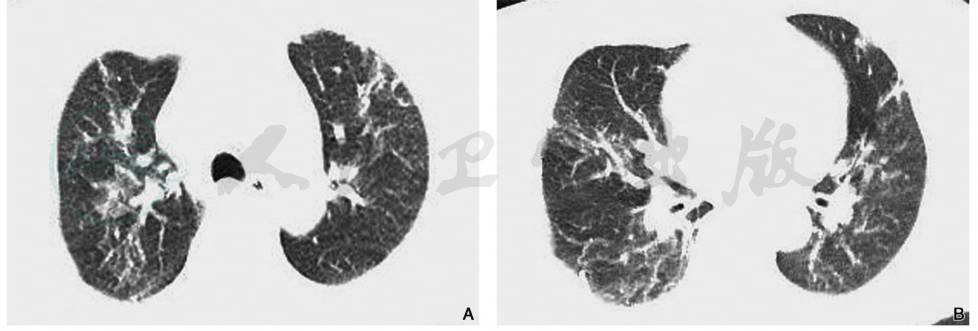

肺挫伤的主要CT表现为创伤应激引起肺间质和肺实质内的液体渗出,可分肺间质型和实变型。多在创伤后1~24小时出现局限性或弥漫性渗出肺泡性和间质肺水肿,以及大片血性渗出的肺实变影。早期CT表现为局部肺纹理增浓,云絮状及弥漫性磨玻璃状密度影,肺内或胸膜下区的无实性成分的或边界模糊的半透明磨玻璃状密度影为其特征性表现,其内尚可见血管和支气管影(图1)。病变可以是单侧、双侧受累,或出现多发性病灶。随局部肺组织内出血性渗出的增多,则可演变为有实性成分的磨玻璃密度影,表现为磨玻璃影内有斑片状影,或表现为大片密度增高实变影,内可见充气支气管影,或形成局部实变的肺血肿。本组实变病变主要分布于下肺基底部,并伴有不同程度的胸腔积液和肋骨骨折。

图1肺挫伤

女性,64岁,胸部CT轴位肺窗(A、B)显示两肺野内多发斑片状高密度影,边缘模糊,右侧胸膜局限性增厚

引自:中华影像医学·呼吸系统卷.第3版.ISBN:978-7-117-28903-0.主编: